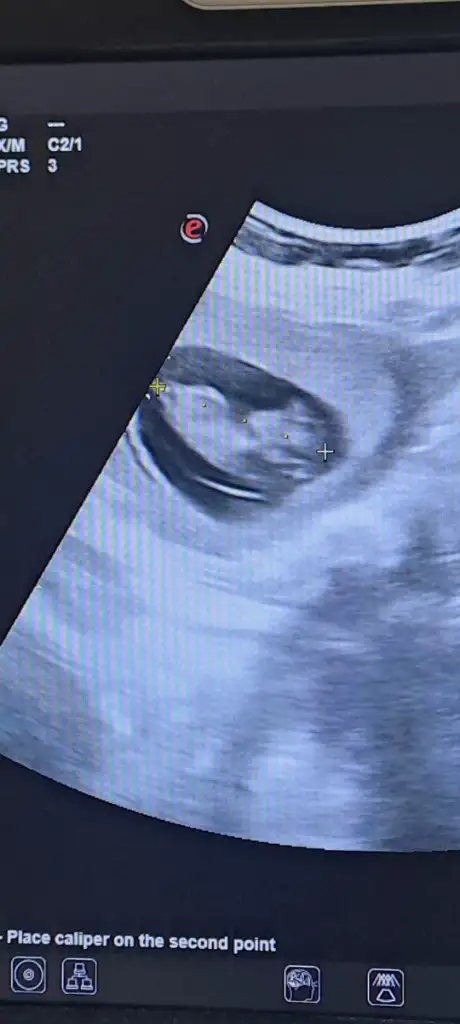

Kızlar lütfen yorum yapar mısınız 15 haftalığz

Benim bebegime de bakar misiniz 16 haftalik görüntüsüBilemedim inanınbelki bilen biri görür yorum yapar sizin için

Merhaba ilk önce rabbim hayırlısını ve gönlünüze göre olanı versin inşallah nub teoremine göre sanki kız gibi

Merhabalar erkek gibi duruyor ama nubda tam aci tam yukari degil hafif yukari skull teorisine gorede erkek gibi duruyor ama tab i Rabbim gonlunuze gore versin insallah tahminim bu Allah bilir gerisini saygilarEki Görüntüle 3587975